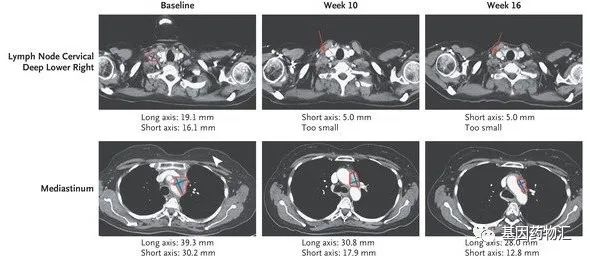

一位55岁的女性非小细胞肺癌患者,接受了sotorasib的临床试验。治疗前,这位患者有2个体积较大的病灶,体积分别为19.1 mm×16.1 mm和39.3 mm×30.2 mm。

治疗10周时,患者的病灶已经非常明显地开始缩小;至16周时,病灶缩小更加明显。